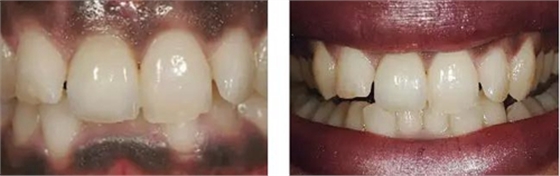

圖10、剛植入種植體當天的情況(左)和植入種植體1年時的情況(右)。

圖11、牙冠戴入1個月以后。軟組織外形良好,形成了良好的弧線形牙齦形態(tài)而沒有瘢痕。保持了原有的色素沉著的顏色和形狀。

圖12、種植術后1年顯示良好的美學效果。